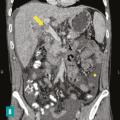

Les maladies vasculaires du foie sont des maladies rares et leur diagnostic peut parfois être difficile, tardif, conduisant à un retard de prise en charge délétère pour le malade. Il est le plus souvent multidisciplinaire, faisant intervenir au premier plan le clinicien mais également le radiologue et l’anatomopathologiste.

Thrombose porte et ischémie mésentérique veineuses

La thrombose de la veine porte (TVP) se caractérise par l’obstruction, le plus souvent par un thrombus, de la veine porte et/ou de ses branches portales (droite et/ou gauche). Cette obstruction peut être partielle ou complète, récente (moins de six mois) ou chronique (plus de six mois) et peut également affecter les vaisseaux…